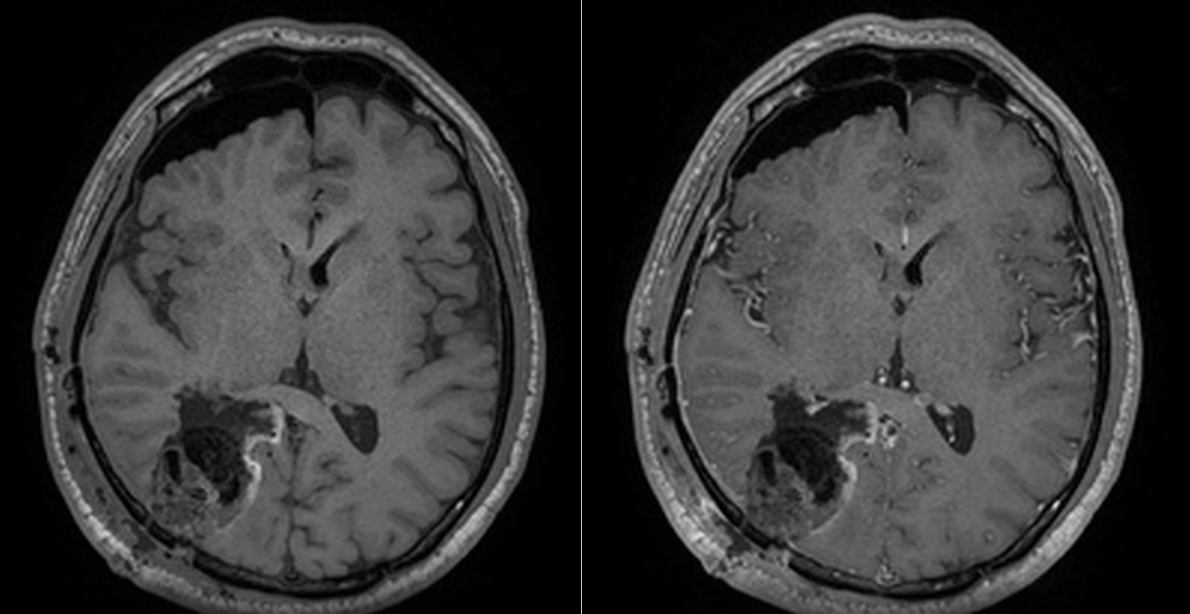

Controalele imagistice s-au repetat periodic, fiecare RMN fiind un moment de emoție și speranță.

Astăzi, la 9 ani de la operație, nu există semne de recidivă tumorală. Deficitul vizual s-a stabilizat, iar dificultățile de recunoaștere a fețelor s-au ameliorat parțial. Mai important însă, pacientul și-a recâștigat viața de zi cu zi.